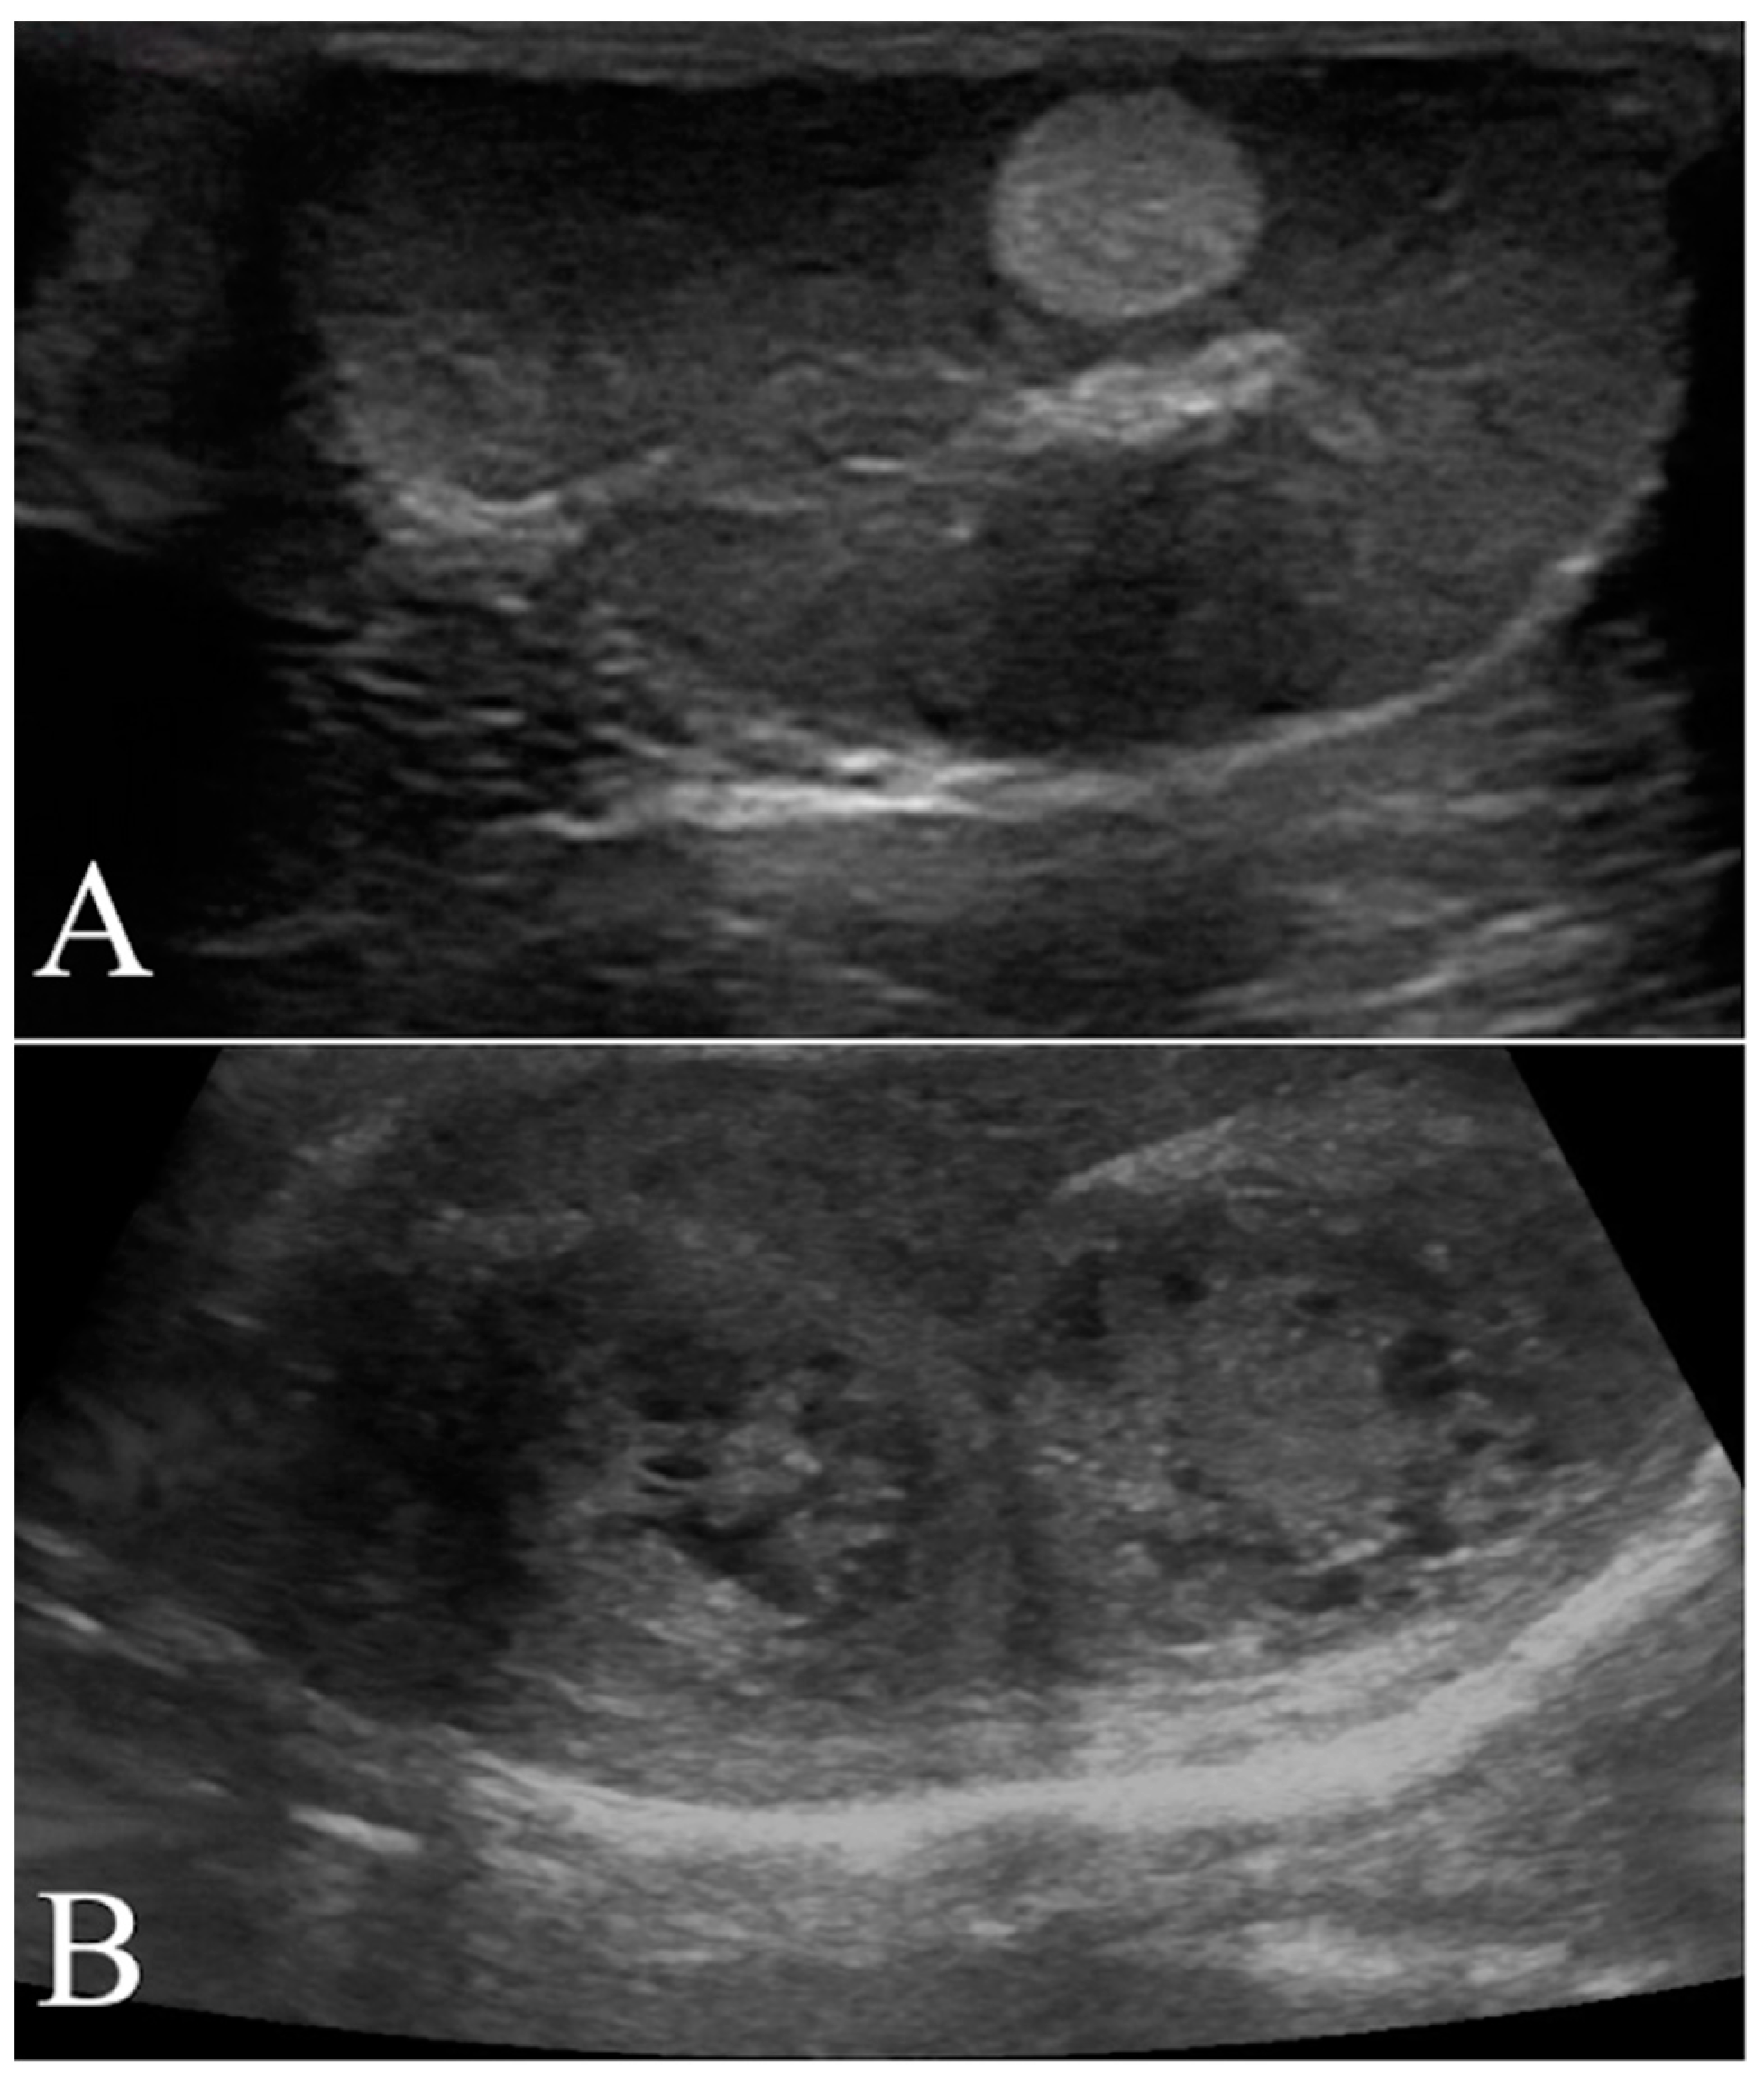

The testicular artery was first detected in the pampiniform plexus by scanning the cranial pole of the testis. Then, the linear probe was moved towards the ventral region of testis to locate the marginal artery. Finally, the ultrasound beam was oriented to optimize the visualization of any lesions present and characterize their blood flow. Based on color Doppler imaging, the blood flow of the lesion was classified as either absent or present and, in such a case, as peripheral or intralesional (Figure 2A). Using pulsed wave mode, a sample volume was successively placed on the pampiniform plexus as well as marginal and lesion arteries (if present) to record the waveforms of at least three consecutive cardiac cycles. The PW was set as follows: frequency 3.1 MHz, pulse repetition frequency 3.3 kHz, and Gain 41 dB. The sample volume, the region where the vessel was studied, was positioned in the artery that allowed the best insonation angle when both peri and intralesional vessels were detected simultaneously in the same lesion. The insonation angle between the Doppler stream and the course of the vascular segment was manually aligned and the measured blood flow velocity was automatically corrected. The measurements with an angle >20° were disregarded. However, the measurements of three different waveforms in each vessel were taken and we made an average to reduce any errors. For each testicular artery, quantitative blood flow analysis included the evaluation of peak systolic velocity (PSV), end diastolic velocity (EDV), resistance index (RI), and pulsatility index (PI) (Figure 2B).

Figure 2. Representative Doppler characterization of a nodular lesion (leydigoma) found in the left testicle of a 11 year old Italian Mastiff. In particular, picture 2 (A), recorded by color Doppler, allowed the visualization of blood flow distributed peripherally to the lesion, while picture 2 (B) showed the same blood flow sampled by pulsed wave mode for quantitative analysis.